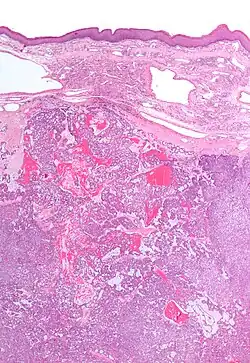

Low magnification micrograph of a polymorphous low-grade adenocarcinoma, showing the typical variation of architectural arrangement. H&E stain.

PLGAs consist of a monomorphous cell population that has a varied histologic morphology.

Microscopically, its histology can be confused with an adenoid cystic carcinoma and a pleomorphic adenoma.